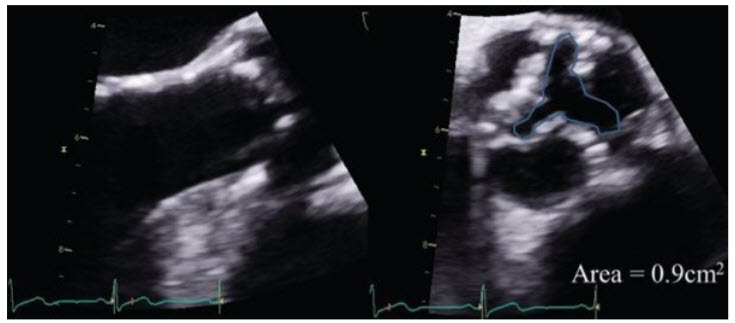

A 76-year-old woman is referred to your clinic with recent onset of exertional chest pain. She has a long-standing history of hypertension and atrial fibrillation. On examination, her body surface area is 2.0 m2 , BP is 150/100 mmHg, and heart rate is 80 to 90 bpm and irregular. The carotid upstroke is delayed and diminished. The apex beat is nondisplaced but sustained. S1 is normal, and S2 is soft and paradoxically split. There is a grade II/VI ejection systolic murmur heard best at the right upper sternal border that radiates to the carotids. An echocardiogram reports normal ejection fraction with a stroke volume of 55 mL. The peak and mean gradients across the aortic valve are 44/28 mmHg. The dimensionless index is 0.21 and the calculated aortic valve area is 0.83 cm2 . You review the echocardiogram (Fig. below)

and confirm the accuracy of the left ventricular outflow tract (LVOT) diameter and are satisfied that multiple windows were used to obtain the gradients.

The rate of mortality, for a patient with these findings, is higher compared with patients with severe AS and high gradients across the aortic valve but aortic valve surgery has resulted in better outcomes in these patients. This woman has paradoxical low-gradient, severe AS with preserved ejection fraction. Her clinical history, examination, and 2D imaging of the aortic valve are consistent with severe AS. She has a low indexed stroke volume (<35 mL/m2 ), resulting in low gradients across the AV but the dimensionless index and AVA both are consistent with severe AS. When there is discordant echocardiographic data the accuracy of measurements should always be looked at again; however, in this case, the low gradients are consistent with low-stroke volume. There are currently no guidelines from the ACC or AHA on how to manage these patients; however, the recent 2012 European Society of Cardiology guidelines for valvular heart disease provide a class IIa recommendation for AVR in symptomatic patients with paradoxical lowgradient, severe AS with preserved ejection fraction. A number of studies have confirmed that the rate of mortality is higher in this cohort when compared with patients with severe AS and high gradients but surgery on the aortic valve is associated with significantly better outcomes.